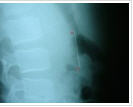

Ngay lập tức, Phước được đưa đi chụp X Quang và kết quả cho thấy chiếc kim may dài 6cm hiện đang nằm dọc trong dạ dày bệnh nhân này.

H́nh ảnh chiếc kim đang trong cơ thể cháu Phước khi chụp X Quang

Lư giải về nguyên nhân trên, người nhà cháu Phước cho biết, do trong lúc vừa kết ṿng hoa vừa ngậm chiếc kim khâu dài 6cm trên môi, khi vừa làm vừa nói chuyện, không may Phước đă nuốt chửng chiếc kim vào bụng. Sau khi phát hiện sự việc, gia đ́nh đă đưa Phước xuống bệnh viện.

Theo các bác sĩ bệnh viện, th́ đây là một tai nạn hy hữu, nếu dị vật ngắn và tù th́ có thể được thải qua đường tiêu hóa. Nhưng do đây là một vật sắc nhọn, dài nên diễn biến rất khó lường và có thể có nhiều biến chứng.

Hiện cháu Phước đang được theo dơi thông qua các phương tiện y tế để biết đường đi của chiếc kim và có hướng điều trị kịp thời.